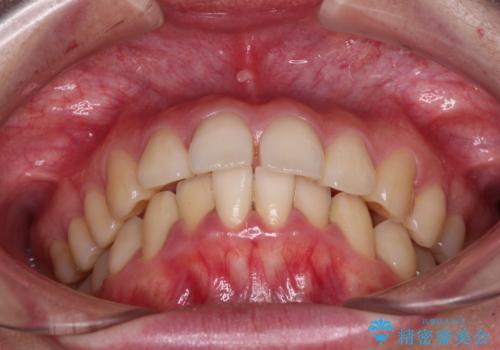

- 下唇に跡がつくほどに飛び出した上顎前歯を気にして来院された患者様です。

来院された時から4本の抜歯が必要であることを理解されていらしており、通法通り上下左右の第一小臼歯4本を抜歯し、ワイヤー装置にて矯正治療を行うこととしました。